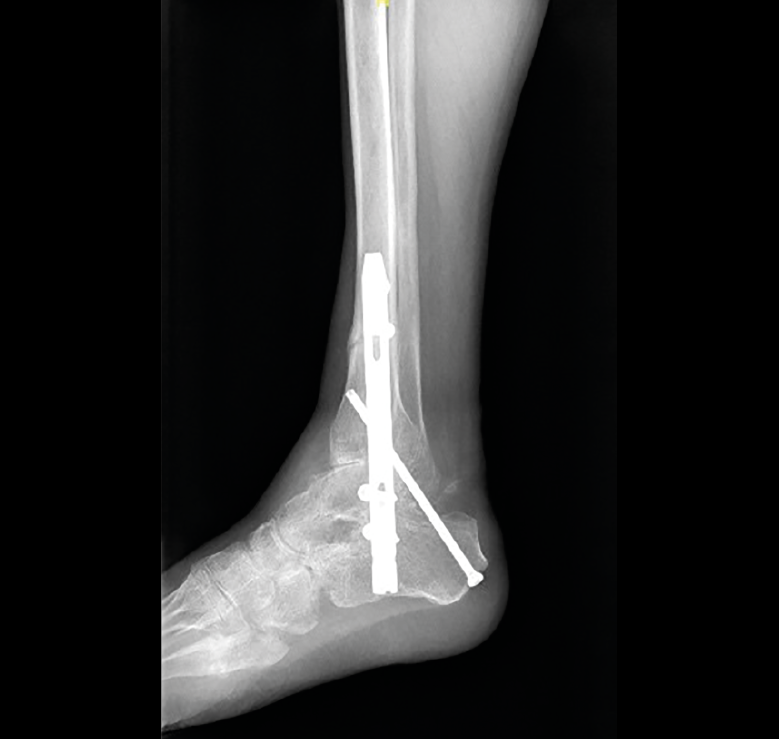

El paciente afecto de poliomielitis presentaba deformidad en equino y varo del retropié. La artrodesis TTC consiguió la correcta alineación y la fusión de ambas articulaciones. No presentaba dolor al año de la cirugía y para la marcha usaba un bastón debido a la atrofia muscular que presentaba (Figura 2).

Figura 2. Radiografía del caso 4 con imagen de artrodesis de ambas articulaciones.